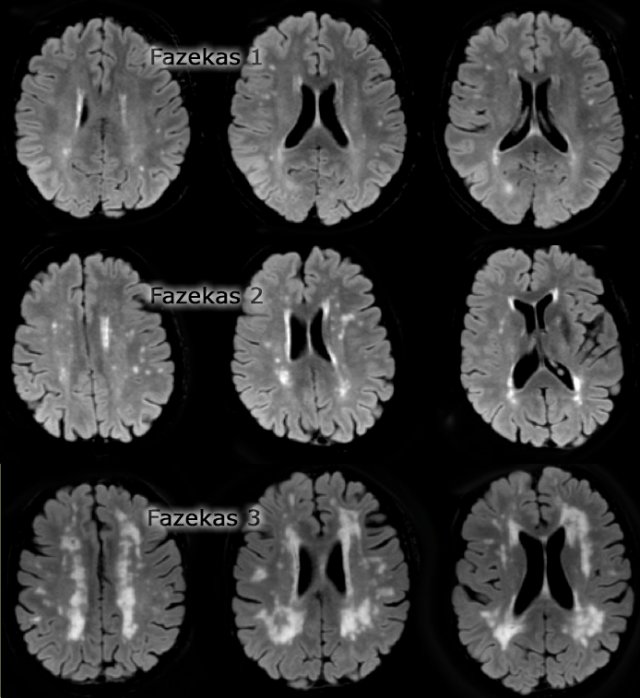

Koedam score for Parietal Atrophy

In addition to medial temporal lobe atrophy, parietal atrophy also has a positive predictive value in the diagnosis of AD.

Atrophy of the precuneus is particularly characteristic of AD (15).

This is particularly the case in young patients with AD (presenile AD), who may have normal MTA-scores.

The Koedam scale rates parietal atrophy - assessed in sagittal, coronal and axial planes.

In these planes, widening of the posterior cingulate and parieto-occipital sulci as well as parietal atrophy (including the precuneus) is rated (Table).

Sagittal T1-, axial FLAIR- and coronal T1-weighted images illustrating the Koedam scale of posterior atrophy.

When different scores are obtained in different orientations, the highest score must be considered (16).